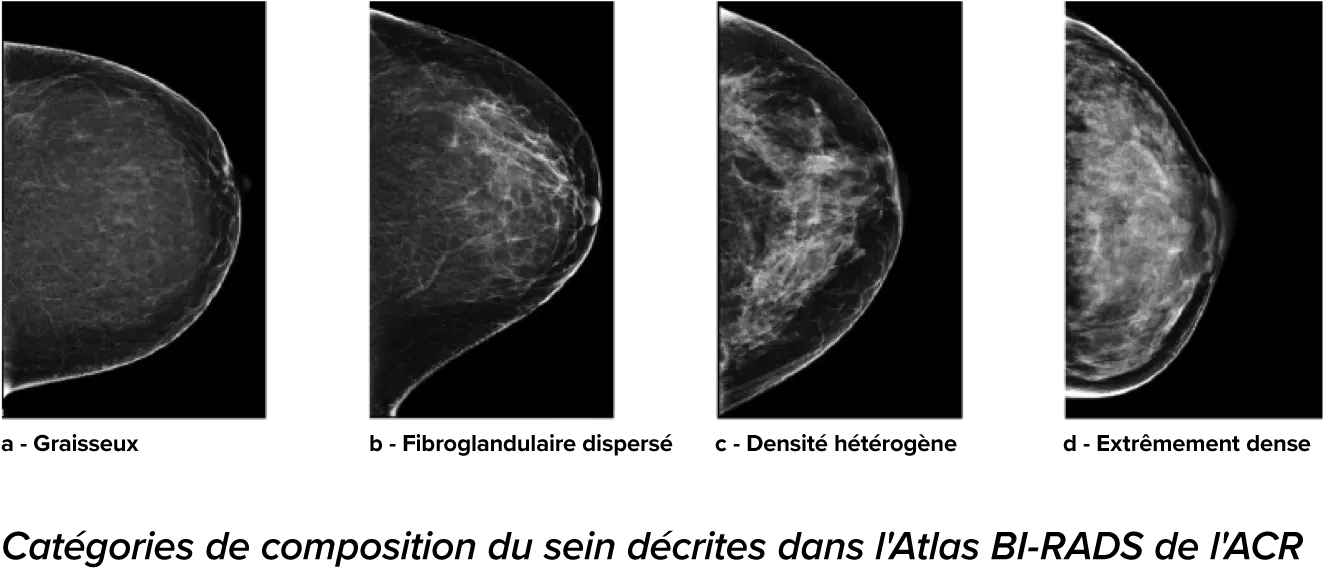

On sait qu’une densité mammaire plus élevée augmente le risque de cancer du sein chez la femme.1 Une analyse précise et objective s’avère donc primordiale. Optimisé par l’apprentissage automatique, le logiciel de la technologie Quantra analyse les images 2D™ et de tomosynthèse pour déterminer la distribution et la texture du tissu parenchymateux. Il classe les seins selon quatre catégories de composition, conformément aux recommandations de l’American College of Radiology (ACR) BI-RADS Atlas 5th Edition.2

Catégories de composition du sein décrites dans l’ACR BI-RADS Atlas.